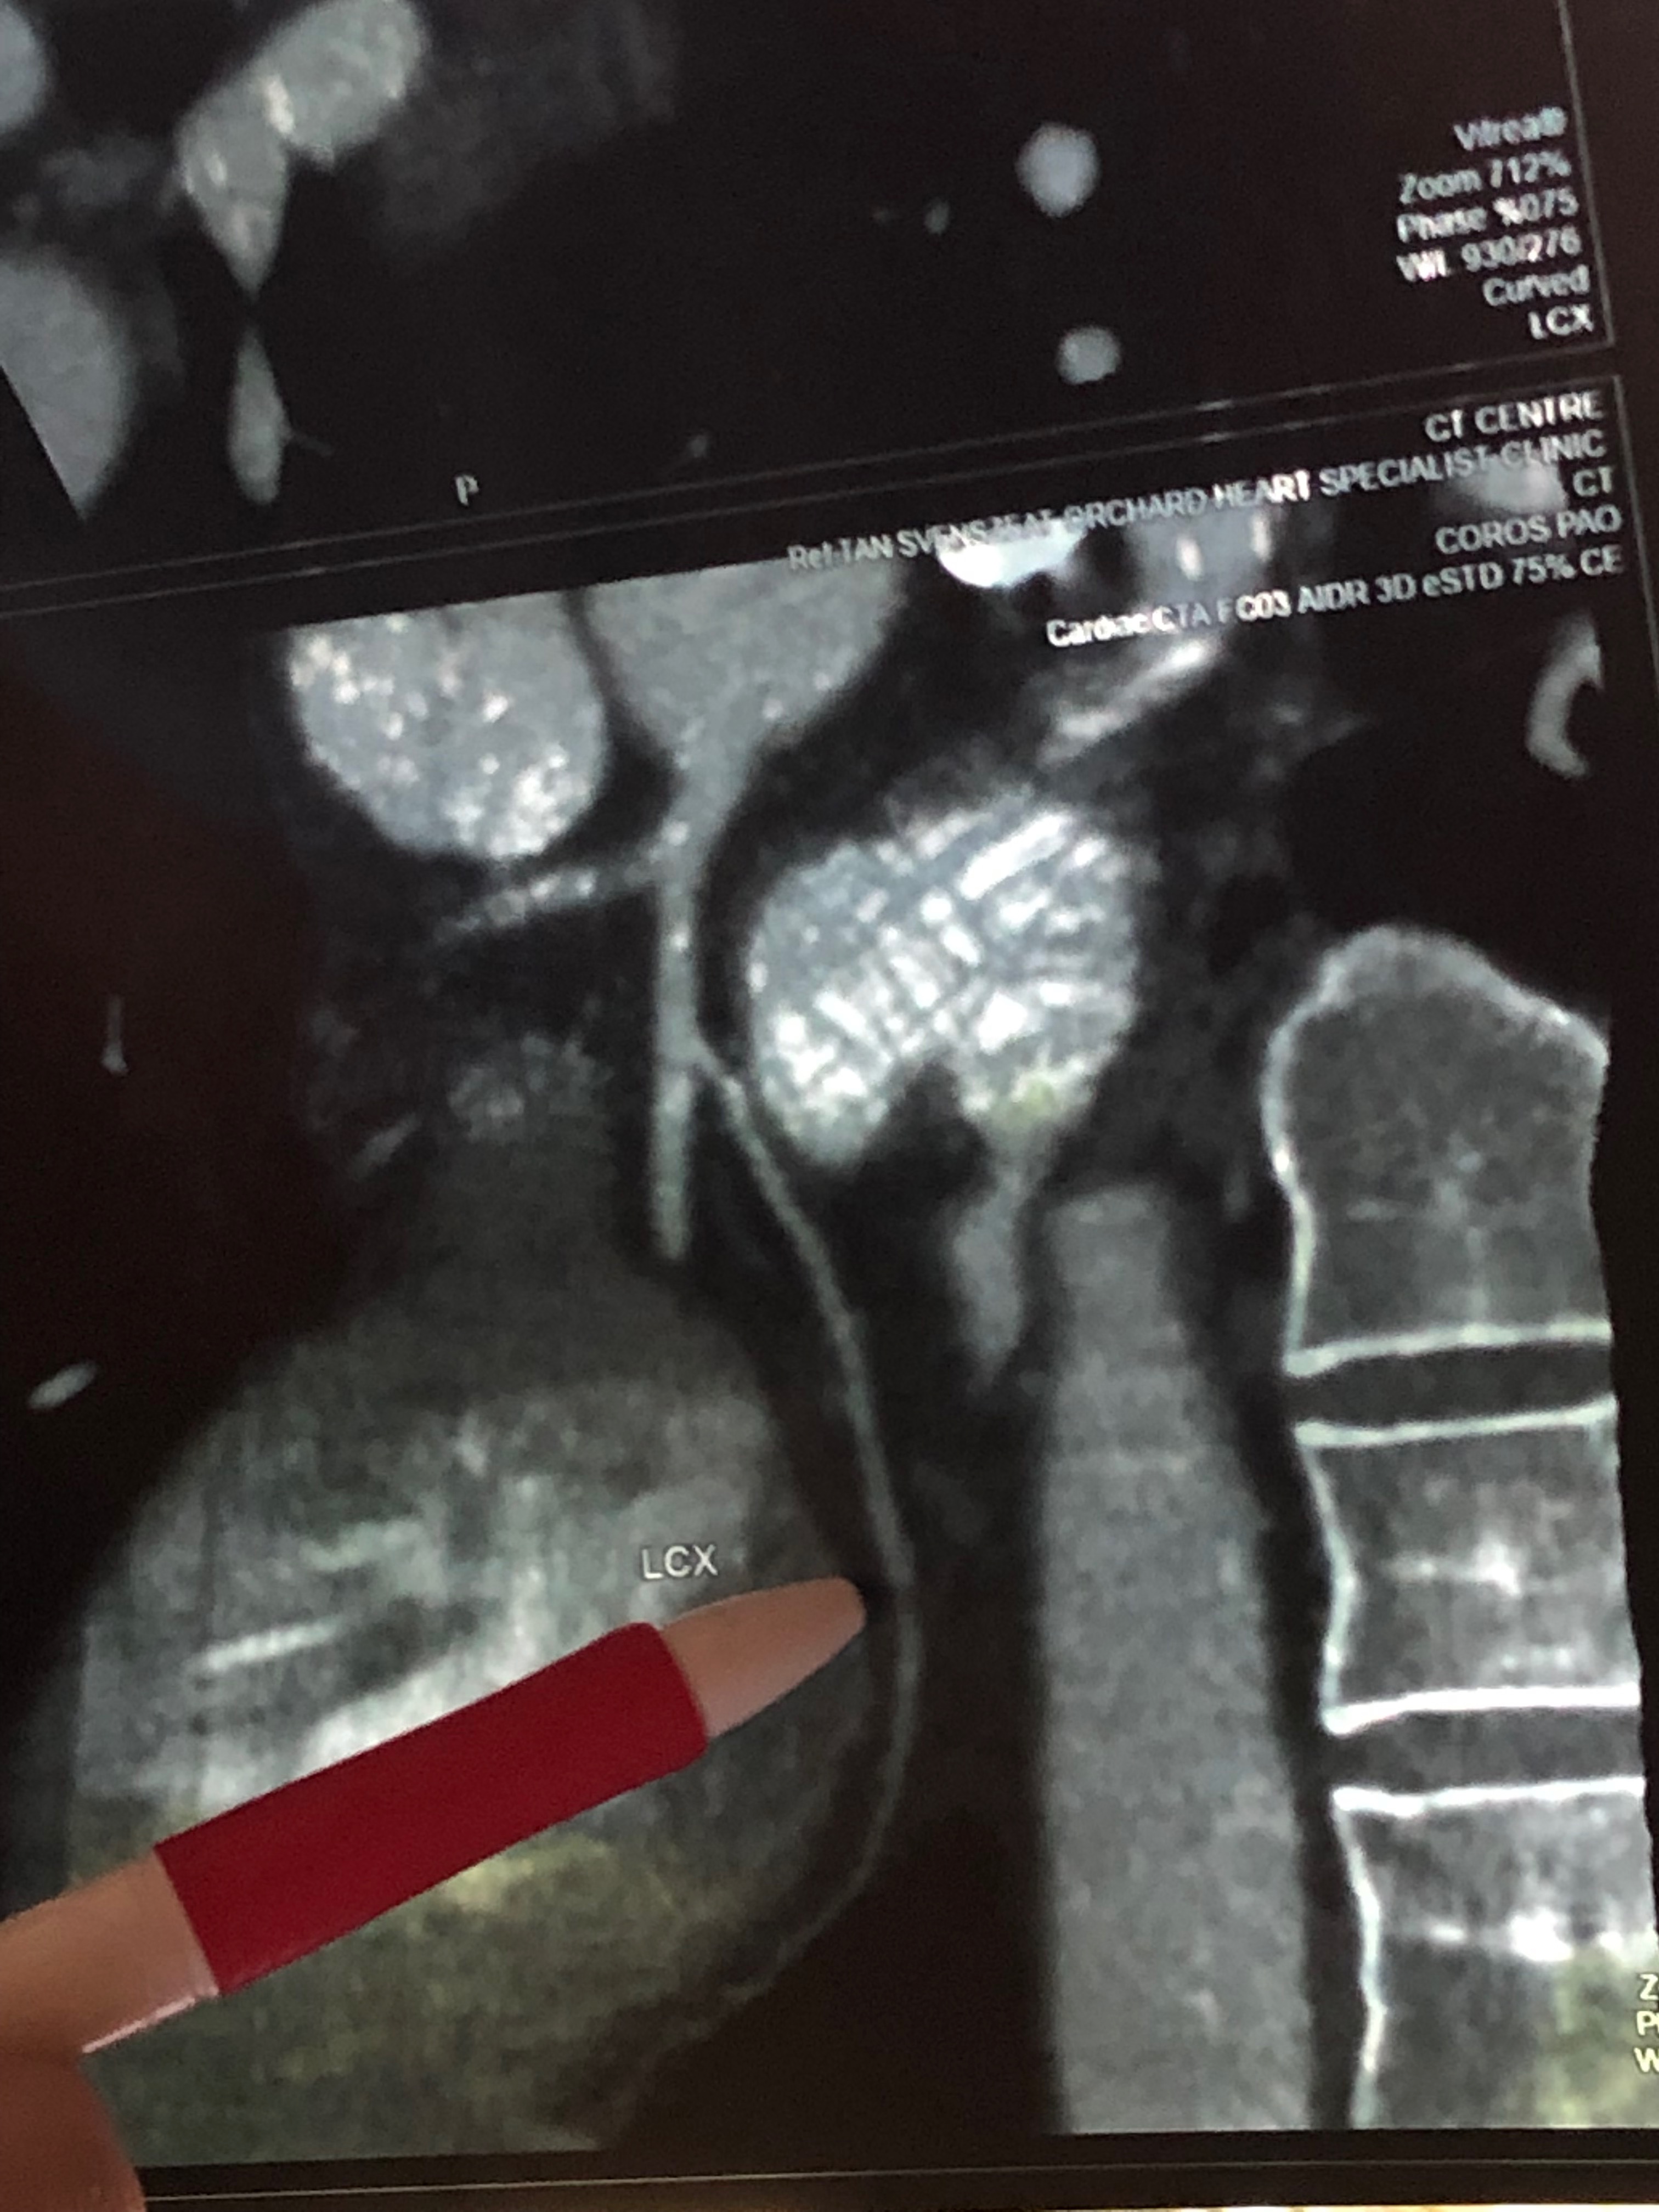

The next morning the CT scan finally took place. They injected contrast into the bloodstream and you can feel the liquid moving through your veins all the way down the groin. It was strange. So here’s what showed up. The pencil points at the black spot which approximates a 99% blockage of the Left Circumflex Artery. I was gobsmacked!